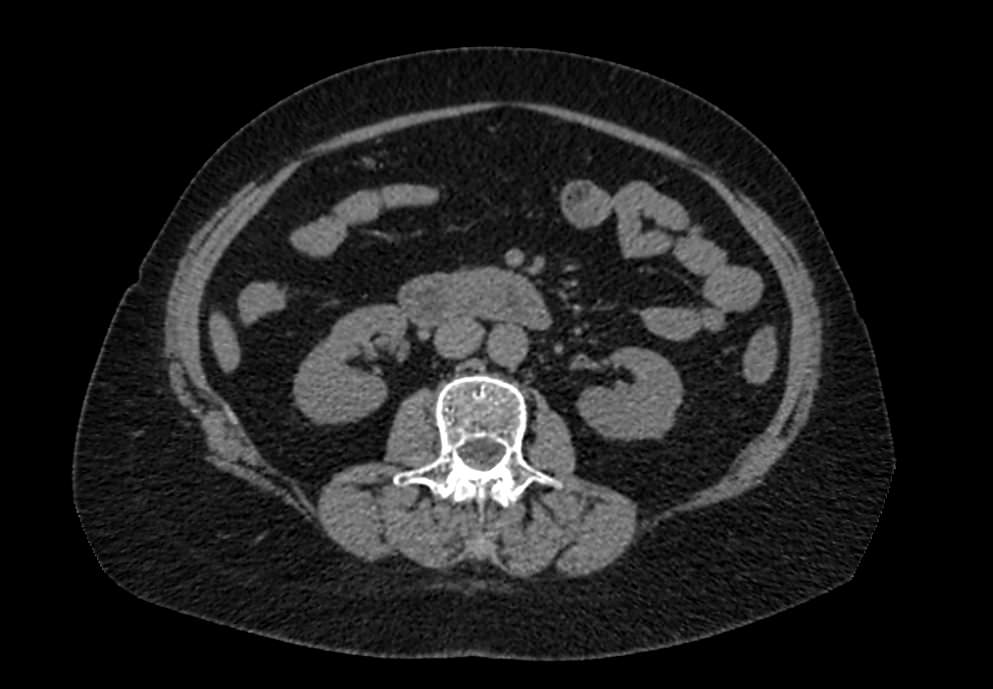

Мультиспиральная компьютерная томография (МСКТ) брюшной полости относится к современным лучевым методам исследования, с помощью которого можно оценить состояние органов брюшной полости (печени, желчного пузыря, поджелудочной железы, селезенки), прилегающих к ним кровеносных сосудов и лимфатических узлов.

С помощью мультиспиральной компьютерной томографии проводятся послойные рентгеновские снимки исследуемой области с толщиной среза от 0,5 мм. В нашей клинике исследование выполняется на компьютерном томографе экспертного класса TOSHIBA AQUILION CXL, который оснащен 128 детекторами, позволяющими получать за несколько секунд снимки брюшной полости с высокой точностью. Большое количество детекторов позволяет получить точные данные, при этом сократить время исследования и сделать минимальной лучевую нагрузку на пациента. Кроме того, инновационные технологии аппарата дают возможность сформировать объемную модель органа и окружающих структур, что также способствует проведению точной и достоверной диагностики.

При подозрении на опухоли, воспалительные процессы, гнойные очаги назначается КТ брюшной полости с внутривенным болюсным контрастированием. Для этого пациенту внутривенно вводится рентгеноконтрастное вещество на основе йода. Благодаря усиленному кровоснабжению препарат накапливается в структуре патологических образований и помогает врачу-рентгенологу выявить изменения в структуре внутренних органов.

Метод контрастирования помогает максимально точно выявить очаг патологии уже на начальной стадии, а также установить его локализацию, точные размеры, форму и особенности кровоснабжения.